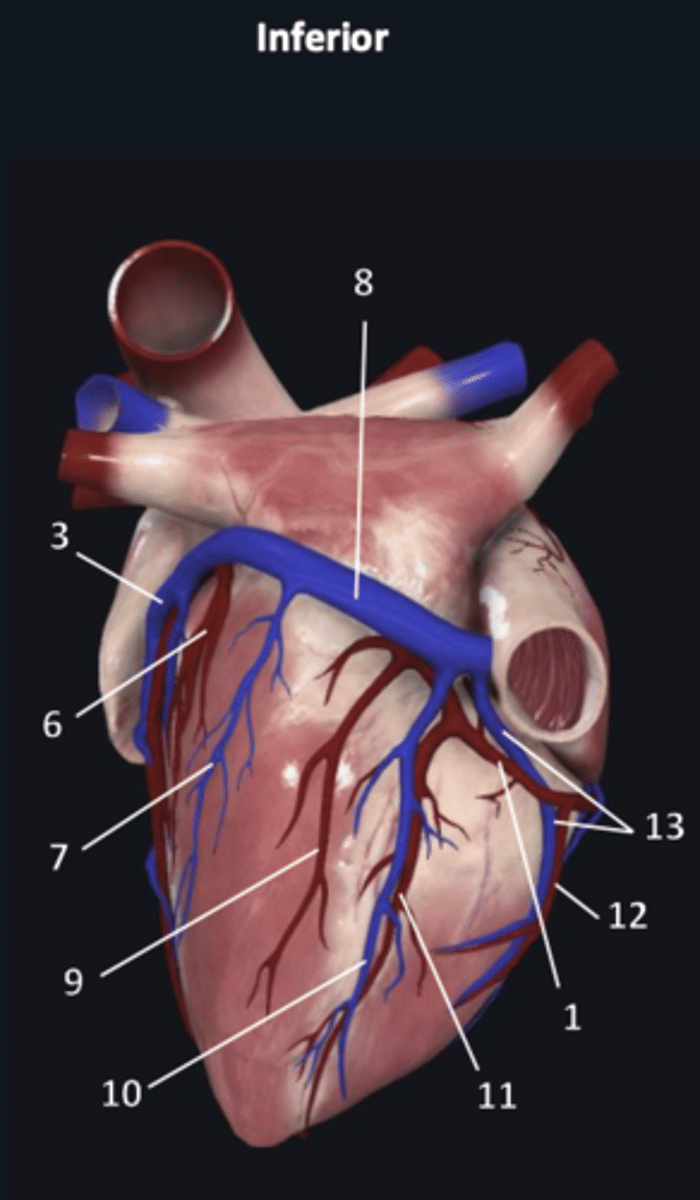

right coronary artery

1

anterior interventricular artery

2 (red)

great cardiac vein

3 (blue)

anterior interventricular artery

2 (red)

great cardiac vein

3 (blue)

left marginal artery

4

left marginal vein

5

posterior left ventricular artery

6

posterior vein of left ventricle

7

coronary sinus

8

right coronary artery

1 (red)

great cardiac vein

3

posterior left ventricular artery

6

posterior vein of left ventricle

7

coronary sinus

8

right posterolateral artery

9

middle cardiac vein

10

posterior interventricular artery

11

right marginal artery

12

small cardiac vein

13